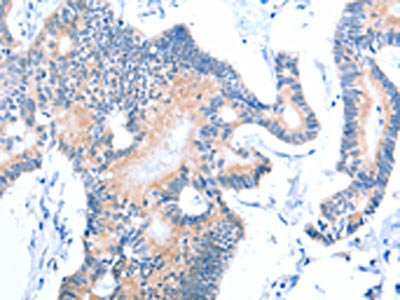

ACAD11 Antibody

Tested Applications: ELISA, WB, IHC; ELISA:1:1000-1:2000, WB:1:200-1:1000, IHC:1:15-1:50

Tested Applications: ELISA, WB, IHC; ELISA:1:1000-1:2000, WB:1:200-1:1000, IHC:1:15-1:50